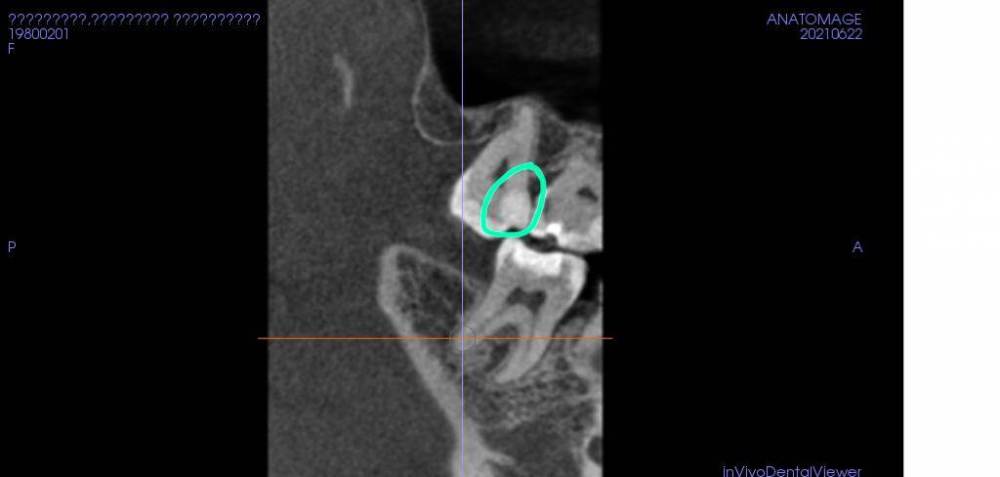

3. Прикрепляю КТ той же области (сделан print screen).

Врач недавно (неделю назад) лечила 7ку сверху, область обведена зеленым, но не видела и не затронула область под старой пломбой на 6ке - только на КТ видна эта область под старой пломбой.

На следующий прием стоматолог приглашала уже лечить другие зубу и 6ка была оставлена без всякого внимания! Если бы не сделанное КТ совсем по другому случаю.